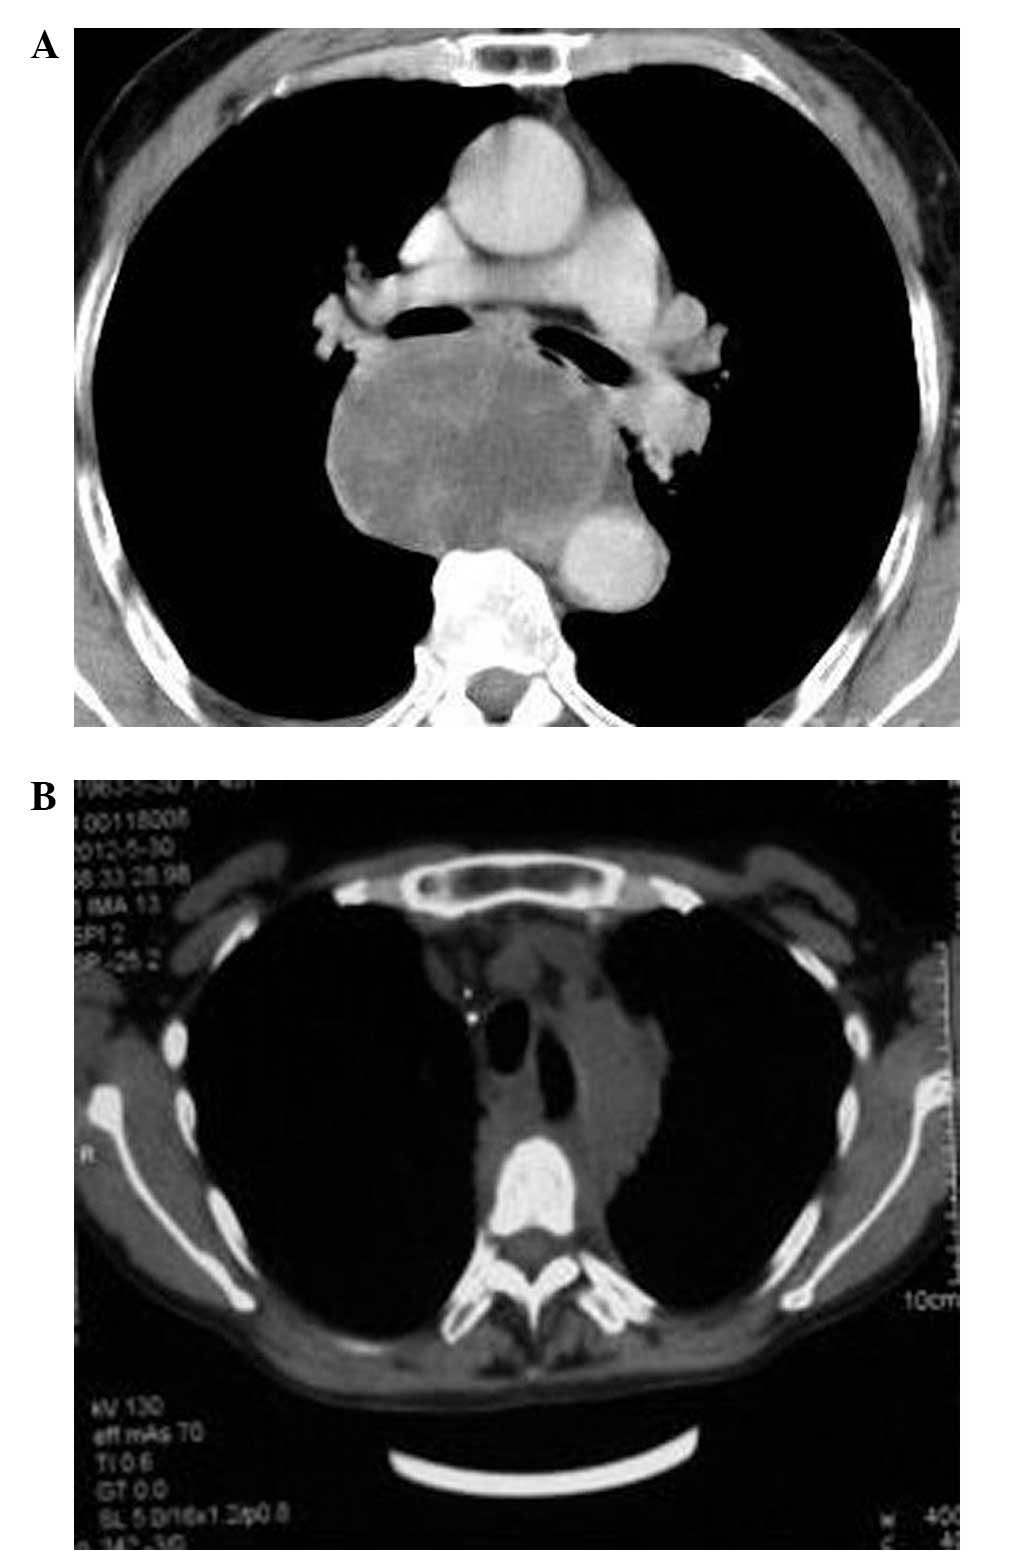

32 hours ago  · PATIENT NAME: Debra Jones: ID NUMBER: 240804: REFERRING PHYSICIAN: Harry Richard, M.D. REFERRING PHYSICIAN’S FAX: 305-123-4567: DATE OF SERVICE: 12/01/10: DOB: CT OF THE UPPER ABDOMEN WITH CONTRAST: ... The aneurysm at the level of the aortic hiatus is described on the CT chest report. This aneurysm also contains a large amount of mural … >> Go To The Portal